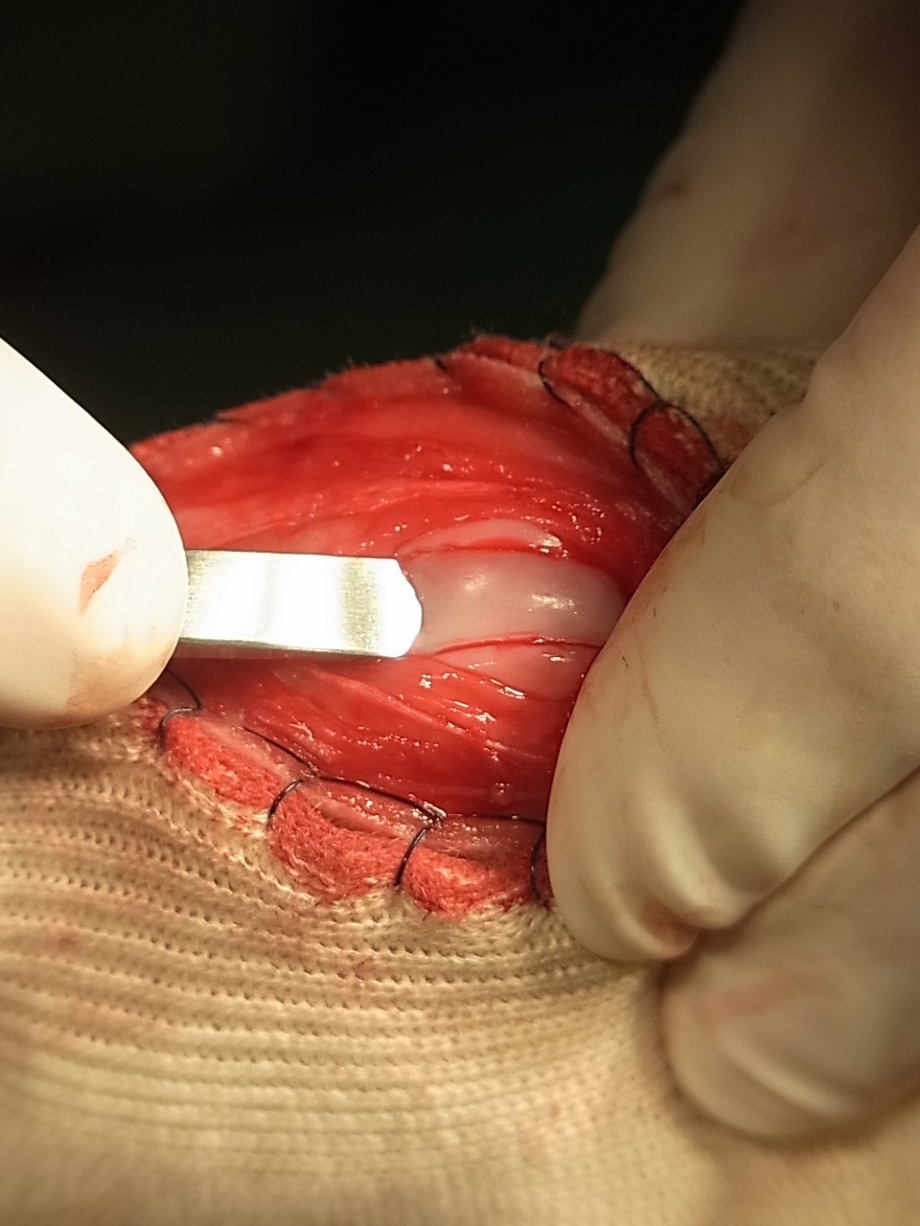

関節包を縫合したところです。関節包は強度があまりありませんので縫縮する必要はありません。

外側の筋膜を鱗状に被せ膝蓋骨を覆うように縫合し外側にテンションがかかるように縫縮します。